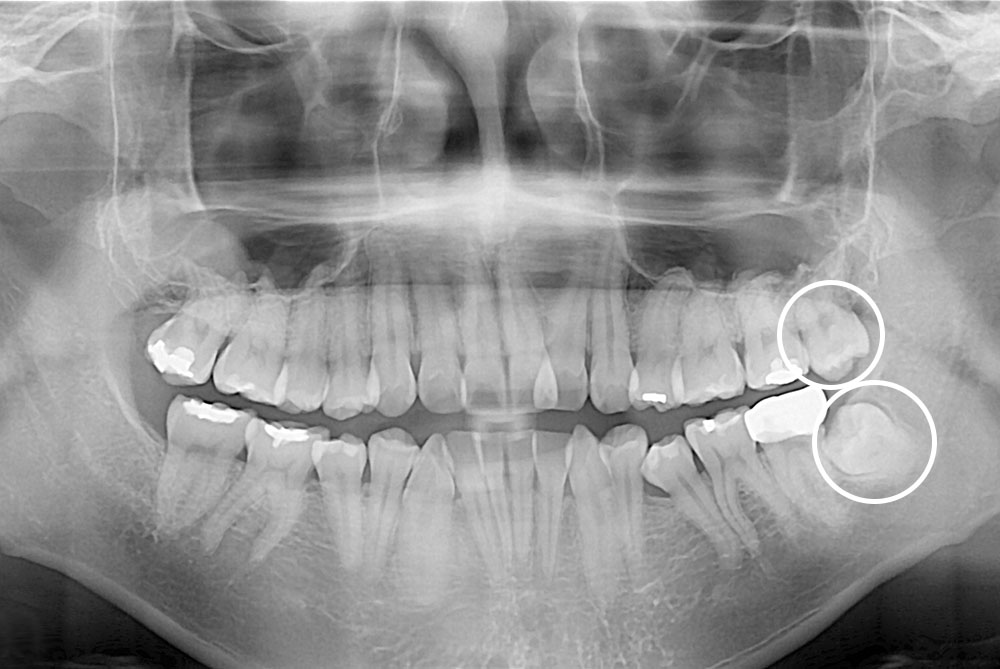

[사랑니] 매복 사랑니 발치

치료전 : 2018-11-23